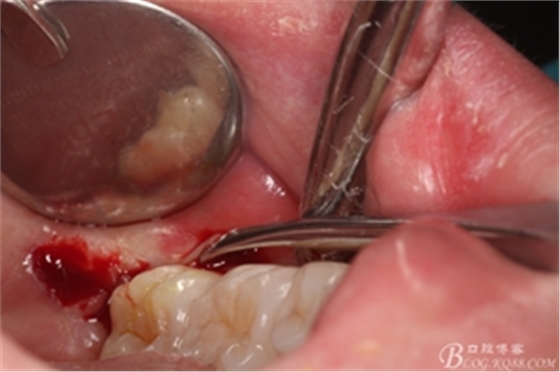

圖6.麻醉效果確定后,在37的近中做垂直松弛切口+遠(yuǎn)中水平切口

圖7. 遠(yuǎn)中的水平切口